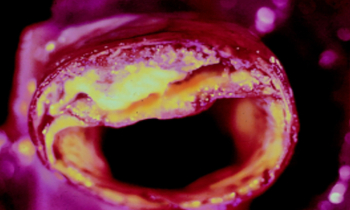

Artères bouchées

Bien-être

Si vos artères sont bouchées, sachez qu’il existe trois ingrédients efficaces qui peuvent améliorer, voire déboucher, les artères bouchées et éliminer la graisse du sang.